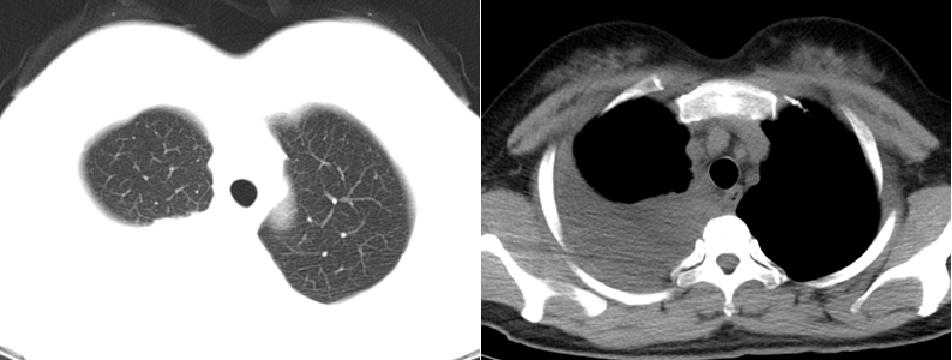

2. 血行播散性肺结核:急性血行播散性肺结核表现为两肺均匀分布的大小、密度一致的粟粒阴影;亚急性或慢性血行播散性肺结核的弥漫病灶,多分布于两肺的上中部,大小不一,密度不等,可有融合。需与电焊工尘肺、肺转移瘤等其他疾病鉴别。

*血行播散性肺结核:均匀分布的大小、密度一致的粟粒结节